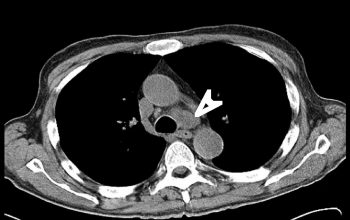

Το ενδοβρογχικό υπερηχογράφημα είναι μια σχετικά νέα διαγνωστική τεχνική που μπορεί να χρησιμοποιηθεί για τη διερεύνηση βλαβών στους πνεύμονες ή στην περιοχή του θώρακα και μεταξύ των πνευμόνων. Πρόκειται για μια δύσκολη περιοχή για να απεικονιστεί και αυτό που κανονικά γίνεται με τη χρήση ενός συνδυασμού των ακτίνων Χ, αξονικής τομογραφίας και βρογχοσκόπησης, μπορεί να επιτευχθεί με το ενδοβρογχικό υπερηχογράφημα (τρεις εξετάσεις σε μία). Μέχρι πρόσφατα, προκειμένου να επιτευχθεί μια αξιόπιστη διάγνωση φυματίωσης, λεμφώματος, σαρκοείδωσης ή καρκίνου πνεύμονα χρειαζόταν παρακολούθηση του ασθενούς ή μια επεμβατική βιοψία στο χειρουργείο. Σήμερα μπορούμε να έχουμε μια βρογχοσκόπηση με ενδοβρογχικούς υπερήχους, όπου θα παρθούν στοχευμένα δείγματα ιστού από το σημείο της βλάβης και θα έχουμε αποτέλεσμα άμεσα από ταχεία βιοψία χωρίς να χάνουμε πολύτιμο χρόνο στη διάγνωση και αντιμετώπιση της ασθένειας. Πρόκειται για μια εξαιρετικά αξιόπιστη εξέταση που πραγματοποιείται ταχύτατα (30 λεπτά) και με ασφάλεια.

- Όταν η αξονική τομογραφία θώρακος αποκαλύπτει ότι ορισμένοι από τους λεμφαδένες στο κέντρο του στήθους είναι διογκωμένοι. Αυτό μπορεί να είναι ένα σημάδι του καρκίνου του πνεύμονα ή σαρκοείδωσης, φυματίωσης ή λεμφώματος.

Παραδείγματα πότε μπορεί να βοηθήσει η εξέταση (ΕBUS) στη διάγνωση

Εικόνες από τη διαδίκασια της ταχείας βιοψίας μέσα στην αίθουσα ενδοσκόπησης